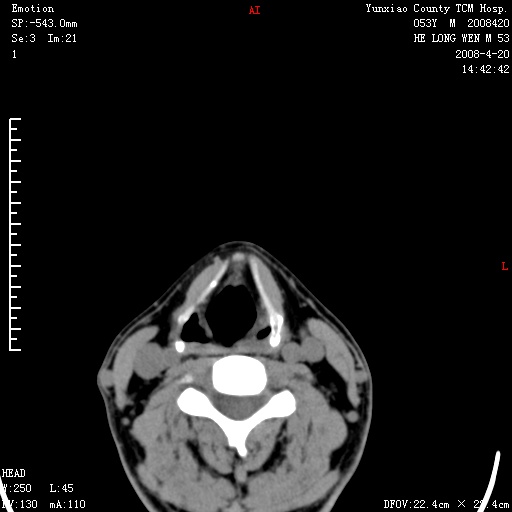

双侧扁桃体肿大:考虑化脓性扁桃体炎。

双侧扁桃体肿大 ,考虑扁桃体炎。

双侧扁桃体肿大,建议结合临床!

双侧扁桃体肿大 ,考虑扁桃体炎

能强化就强化,不能强化就喉镜检查。如怀疑扁桃体肿大,应再往上扫

应该有症状,体检此部位不是常规体检项目,支持双侧扁桃体肿大 ,考虑扁桃体炎,但还是强化一下吧。

双侧扁桃体肿大,考虑扁桃体炎,应做一下增强

显示部分为舌扁桃体,腭扁桃体未见显示。会厌显示欠规则,建议喉镜。